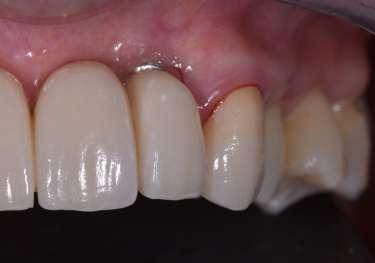

Paziente femmina, 38 anni che presenta carie cervicale dell’elemento 1.5. Gengivectomia con manipolo angolato, tip in zaffiro con diametro di 400 μm, lunghezza 12 mm, 2.4 W, 20 Hz, 120 mJ E per impulso, potenza di picco 750 W, densità di potenza media 659 W/cm2, densità di potenza di picco 205,860 W/cm2, energia totale 432 J, larghezza impulso 160 μs, distanza tip-tessuto 1 mm, 50% acqua, 50% aria, tempo totale di trafamento 180 sec. Impostazioni dello smalto: manipolo angolato, tip in zaffiro diametro 800 μm, lunghezza 12 mm, totale energia 810 J, ampiezza dell’impulso 160 μs, distanza tip-tessuto 1 mm, 100% acqua, 70% aria, tempo di trafamento totale 180 sec.

Fig. 1 – Cavità su 1.5 Fig. 2 – Particolare della cavità del dente 1.5 Fig. 3 – Preparazione Laser Er:YAG Pluser con lunghezza d’onda di 2940 nm di LAMBDA DoctorSmile, Italia. Fig. 4 – Particolare della cavità dopo gengivectomia Fig. 5 – Particolare della cavità completata dopo la preparazione della dentina Fig. 6 – Restauro finale in composito (Asteria Tokuyama, Japan)